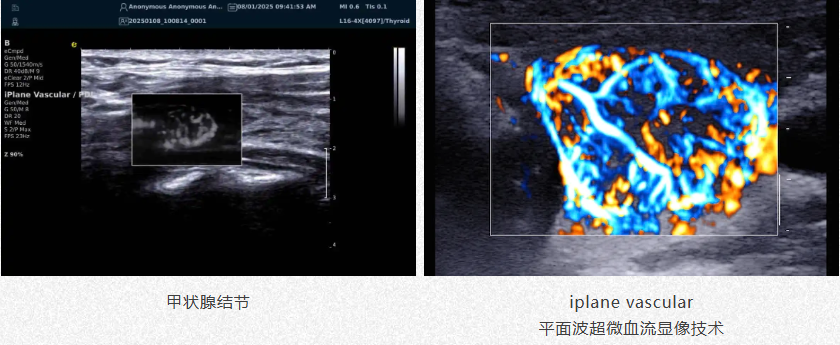

肿瘤良恶性鉴别

1.高效检测出肿瘤微细血管与低速血流,帮助医生早期发现肿瘤并进行良恶性的鉴别诊断。

2.通过血管指数(VI)定量评估肿瘤内部血管,为诊断提供客观依据。

a7d7f728d8905512c0d17a67808bd3e.png